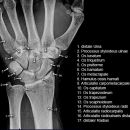

Handgelenk a.p.

Beurteilungskriterien

• Neigung der distalen Radiusgelenkfläche in der Frontalebene: 15 – 35°

• Längenverhältnis Radius – Ulna: Proc.styloideus radii überragt Gelenkfläche der Ulna um 9 –12mm (<9mm Ulna-Plusvariante, >12mm Ulnaminusvariante)

• Kontinuität der drei Karpalbögen:

Proximaler Bogen: proximale Gelenkflächenkonturen von Scaphoid, Lunatum und Triquetum

Mittlerer Bogen: distale Gelenkflächenkonturen von Sacphoid, Lunatum und Triquetum

Distaler Bogen: proximale Gelenkflächenkonturen von Capitatum und Hamatum

Fehlende Abgrenzbarkeit, Versatz oder Unterbrechung sind als pathologisch zu bewerten und deuten auf eine Luxation hin.

Trapezförmige Darstellung des Lunatum in Neutralstellung? Augenzeichen des Hamulus? Superposition von Pisiforme und Triquetum? Metacarpale III in Projektion innerhalb der Radiusgelenkfläche? Lunatum zu >50% über Radiusgelenkfläche? Cave: bei Radial- oder Ulnarduktion wandert das Lunatum in umgekehrter Richtung.

• M-förmiger Verlauf der Gelenkspalten der Carpometacarpalgelenke? Luxationsstellung in den Carpometacarpalgelenken (meist dorsale Luxation)?

• Gelenkspaltweiten des Radiocarpalgelenk 2 – 2,5mm, der Carpometacarpalgelenke 1 –2mm, distales Radioulnargelenk 2mm, Gelenksspaltweiten der Intercarpalgelenke 1,5 – 2mm

Cave: SL-Dissoziation (Ruptur des SL- Bandes, häufigste Gefügestörung): Terry-Thomas-Sign = SL-Spalt > 3mm, Siegelringzeichen = Ringförmige Transparenzminderung im mittleren Scaphoiddrittel durch orthograde Projektion der Taille infolge Rotation.

• Obliteration des Scaphoidfettstreifens?

• Täuschungsmöglichkeiten durch Vielzahl akzessorischer Ossikel (abgerundete, zirkulkär-geschlossene Kortikalis), geteilte Handwurzelknochen (Scaphoid, Lunatum, Pisiforme) und Gefäßkanälchen

• Target areas leicht zu übersehender Frakturen: distales Radioulnargelenk, Processus styloideus radii et ulnae, Basen der Metacarpalia (v.a. MCP I), Hamulus.

• Grundsätzlich gilt: unklare Verhältnisse ->CT-Indikation